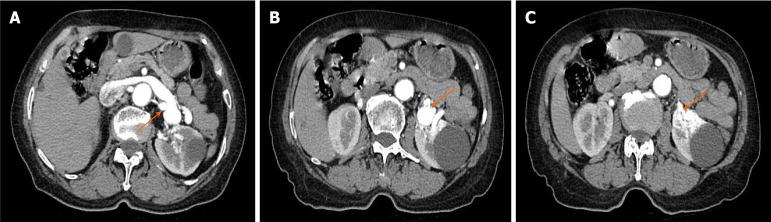

A 69-year-old female patient presented with gross hematuria that had persisted for 10 days. The patient underwent ultrasound examinations of the kidneys and renal blood vessels, enhanced computed tomography, three-dimensional computed tomography angiography, and digital subtraction angiography of the renal arteries. These revealed dilatation of the left renal vein and abnormal shunting between the left renal artery and vein. The patient was diagnosed with a left RAVF using combined multimodal imaging techniques. The patient was treated with left renal artery embolization immediately after renal arteriography. Hematuria resolved following the left renal artery embolization without serious bleeding or other complications. The patient made a full recovery after one year of postoperative follow-up.

Multimodal imaging techniques complement each other when diagnosing RAVF, providing detailed diagnostic information that can aid in accurate diagnosis and treatment. In addition, this case reminds the sonographer to pay more attention to the color doppler flow imaging and blood flow spectrum when examining the kidney, so as to avoid misdiagnosis of renal cystic lesions as renal cysts and missed diagnosis of RAVF.